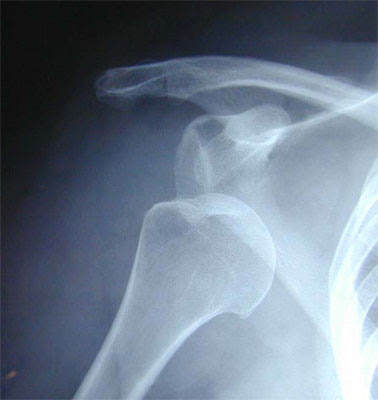

L’articulation de l’épaule est formée de l’extrémité supérieure de l’os du bras (tête de l’humérus), qui glisse dans une cavité peu profonde (la glène) située sur l’os de l’omoplate. Qu’est-ce qu’une tendinite de l’épaule ? La douleur est dite chronique, lorsque la sensation douloureuse excède trois mois et devient récurrente. Epaule , instabilité, butée, Bankart, luxation. Découvrez le répertoire complet des définitions de la symbolique du corps et la signification des symptômes. L’instabilité de l’épaule est une pathologie qui survient après élongation ou rupture des éléments capsulo-ligamentaires qui permettent naturellement de conserver une épaule stable.

Quand nous nous déboîtons quelque chose – luxons est le terme utilisé par les experts – les surfaces de contact de l’articulation sont séparées l’une de l’autre. C’est la plus fréquente des luxations de l’organisme. Il s’agit le plus souvent de la luxation antéro-interne de l’articulation scapulo-humérale : la tête de l’humérus passe en avant et se bloque en dedans du rebord antérieur de la glène. Epaule Préparer son expédition (rando, trek, montagne) Une chute sur l’épaule aboutit très souvent à une lésion appelée disjonction acromio-claviculaire. L’évolution de cette instabilité se fait vers des luxations de plus en plus faciles et fréquentes.

La subluxation antérieure est une luxation antérieure incomplète spontanément réduite. Obtenez un rendez-vous dans votre CIM en quelques jours seulement. Forme normale d’une tête humérale avec un interligne gléno-huméral congruent.

Arrondissement de la tête humérale (signe de l’ampoule) dû à la rotation interne avec perte de congruence de l’interligne.